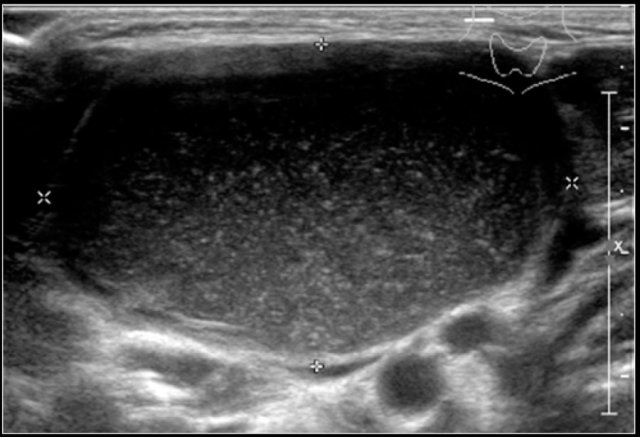

The thymus is located in the upper mediastinum and can be visualized with a suprasternal scan plane.

With increasing age its echogenicity increases and becomes more granular.

Ultrasound is ideal to demonstrate the thymus as a cause of a widened upper mediastinum in infants.

Ultrasound image of the thymus in an eight-year-old boy.